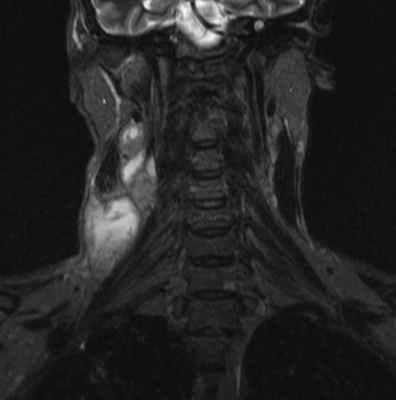

Туберкулезный лимфаденит на снимке МРТ

КТ мягких тканей шеи

КТ сканирование шеи проводят в тех случаях, когда другие

методы исследования оказались малоэффективны и требуется подтверждение

диагноза.

Показания к проведению компьютерной томографии шеи:

травмы этой области;

подозрения на наличие новообразований;

необходимость оценить кровоснабжение и выявить патологию сосудов шеи и головы;

нарушения функции лимфатических узлов;

подозрения на наличие инородного тела в пищеводе, трахее;

заболевания щитовидной железы;

воспалительные процессы исследуемой области.

Томография покажет состояние кровеносной системы, отвечающей за кровоснабжение шеи и головы, визуализирует очаги воспаления, дает возможность определить характер процесса (абсцесс, флегмона, инфильтрат).

Процедура контрастной КТ выявит новообразования и их взаимодействие с

окружающими тканями, поможет дифференцировать злокачественные опухоли шеи,

уточнить местонахождение метастазов.